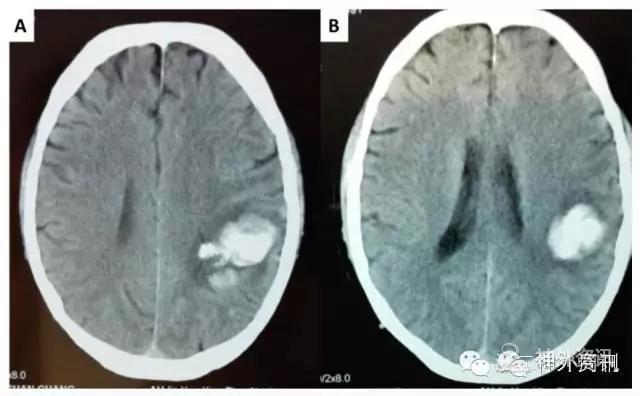

患者3周前无明显诱因出现右上肢麻木伴抽搐,持续约半小时后症状缓解,无意识障碍及大小便失禁等,未予重视。1周前上述症状再次发生,同时出现头痛,遂至当地医院就诊,头颅CT示(图1):左额顶占位性病变伴出血。进一步查DSA显示:左额顶颅内动静脉畸形合并血流相关性动脉瘤。患者为求进一步治疗,转来我院。门诊以“左额顶叶动静脉畸形出血并动脉瘤,继发性癫痫”收入院。

图1. 头颅CT提示左侧额顶叶占位性病变伴出血。